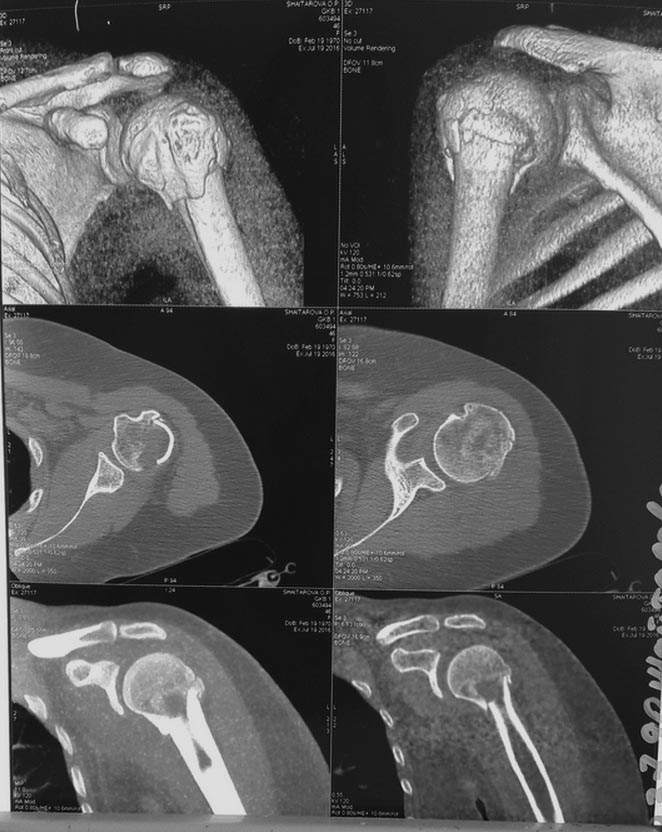

Контроль КТ, выполненной вчера, на фото. По МРТ, выполненной сегодня-данных за повреждение мышц,формирующих вращательную манжету плеча нет. Краевой разрыв лабрум гленоидале в верхне-наружнем квадранте. Умеренно повышенное количество жидкости в суставе,взаимоотношения в субакромиальном пространстве не изменены. Консервативное лечение продолжено, планируем выписку.